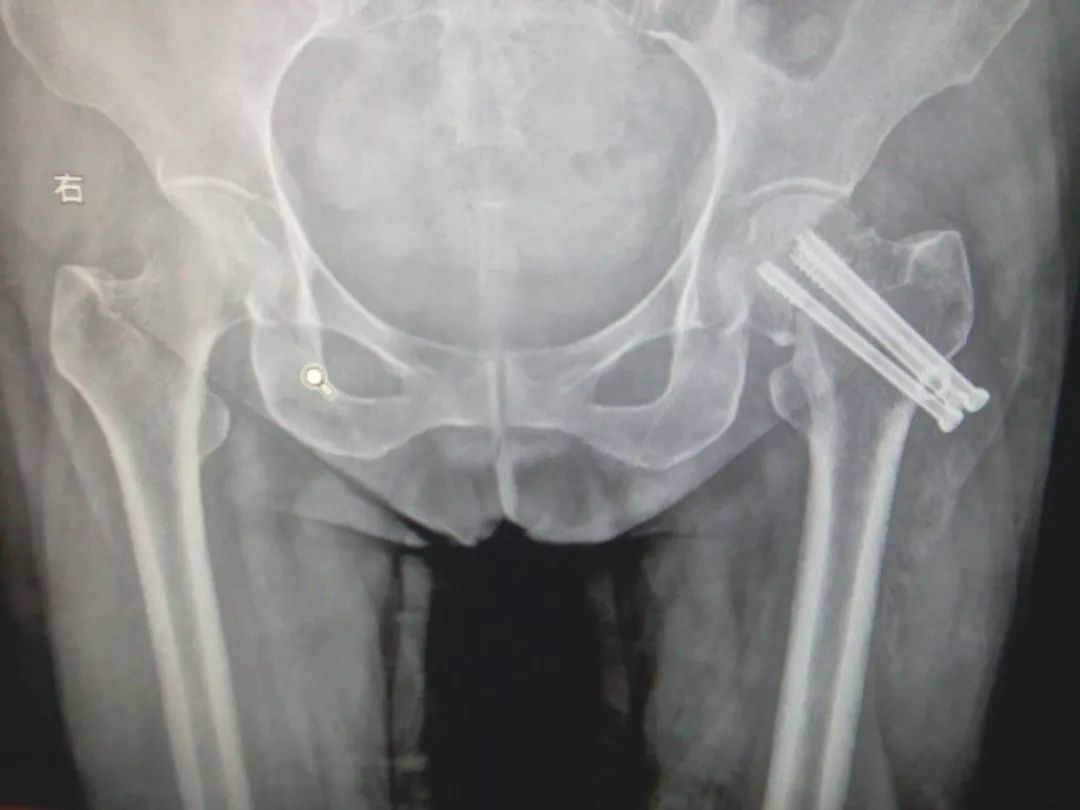

2、外固定。用外固定架治疗。

2、外固定:采用经皮穿钢针固定的外固定架方式治疗。

优点:创伤最小,即使身体条件很差的老年人也可以耐受。

缺点:固定力不足,外固定架不方便,妨碍翻身和活动,也不能早期下地。